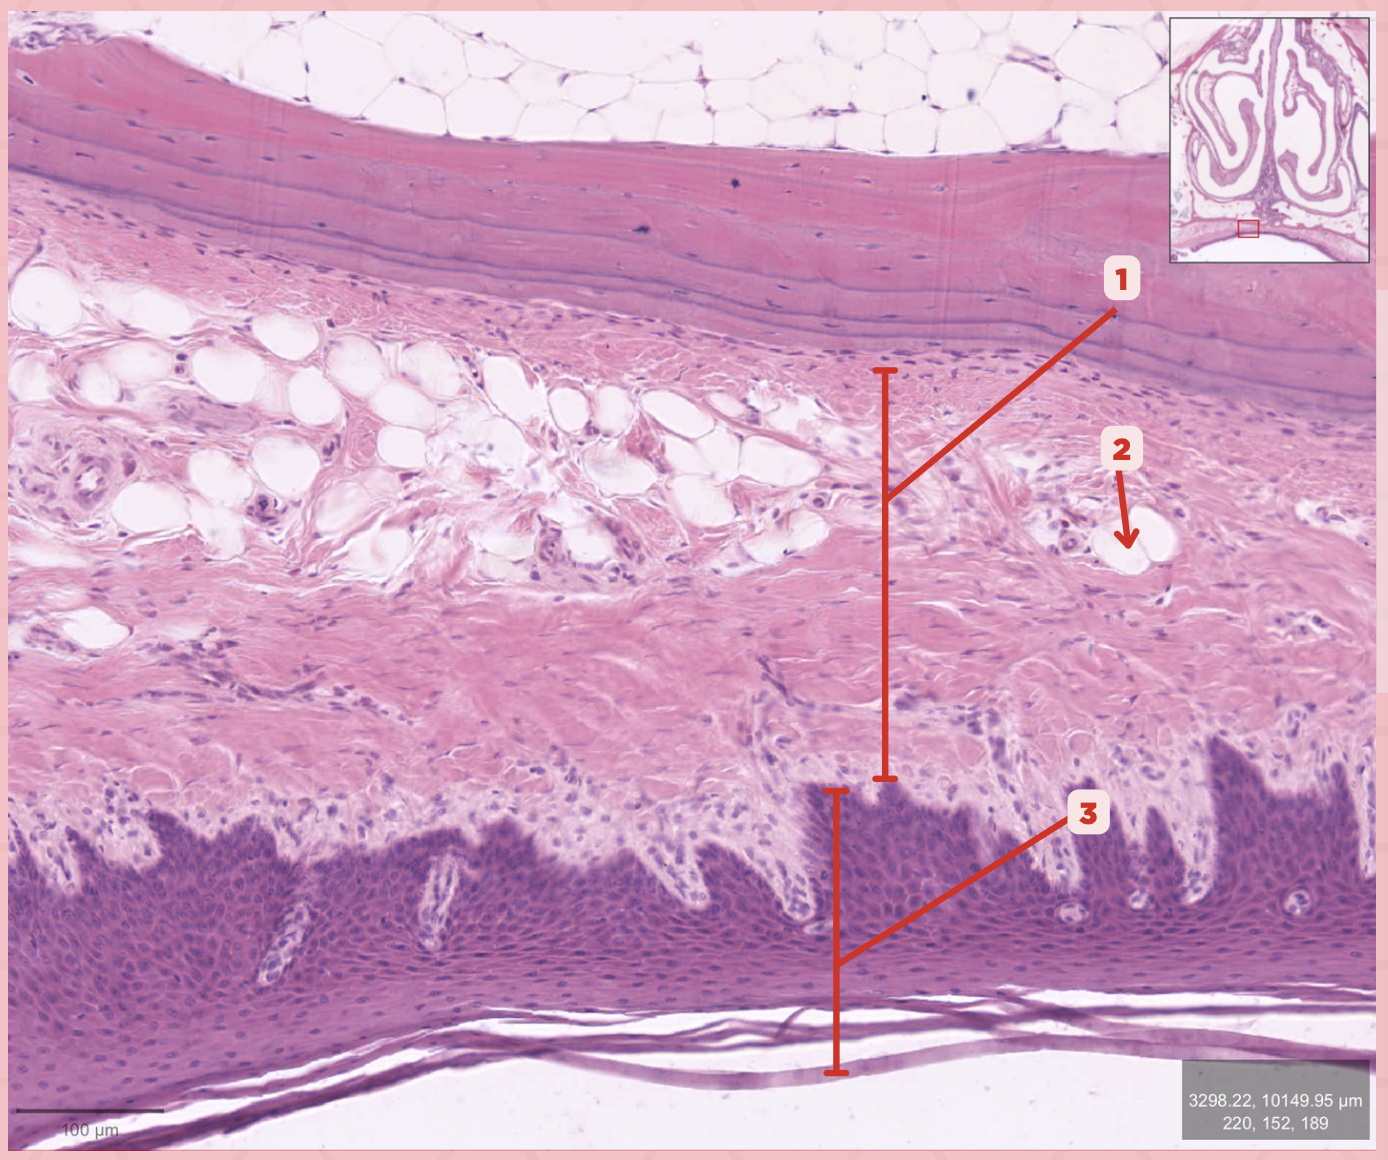

Lamina Propria

Identify the structure labeled as 1.

Adipocytes

Identify the structure labeled as 2.

Keratinized stratified squamous epithelium

Identify the structure labeled as 3.